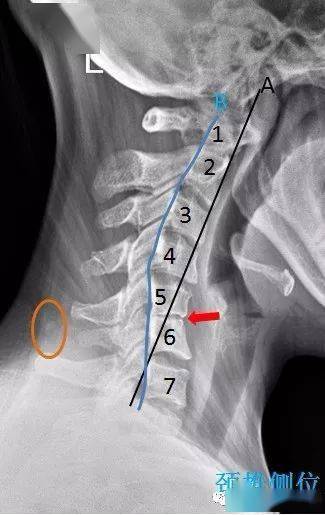

c3/4 椎间孔变窄(双斜位蓝色箭头),c5/6 段项韧带钙化(橙色区域内).